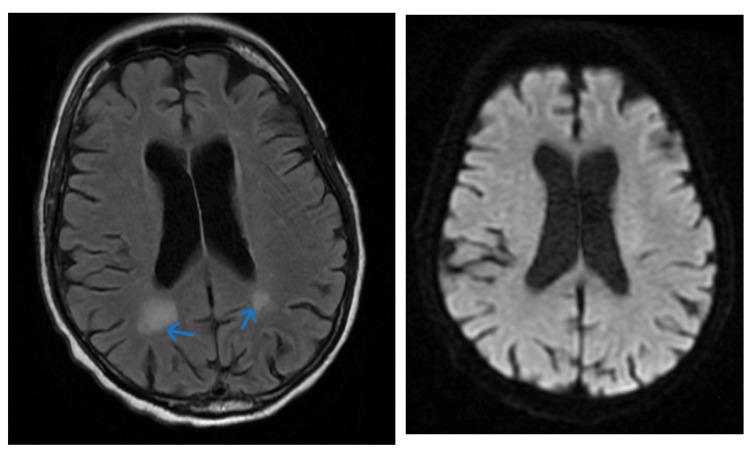

Occipital lobe epilepsies (OLEs) are a subset of epileptic disorders manifesting predominantly with visual and oculomotor abnormalities that are often misdiagnosed due to similarities with migraines with visual aura and other central nervous system (CNS) pathologies. This case study describes an 88-year-old male with a three-week history of intermittent kaleidoscopic visual phenomena, accompanied by blurring of vision and altered level of consciousness. Neurological examination revealed right homonymous hemianopsia and focal neurological deficits, including forced right gaze preference and nystagmus. Diagnostic modalities, MRI and MRA, ruled out ischemic stroke but indicated mild to moderate cerebral atrophy and chronic microvascular ischemic changes. The patient exhibited a seizure episode characterized by right-sided gaze preference and altered consciousness. Postictally, transient right homonymous hemianopsia was observed, consistent with Todd's phenomenon. Treatment with intravenous levetiracetam and lorazepam led to a reduction in seizure frequency. This case highlights the importance of comprehensive evaluation in distinguishing OLEs from other conditions with similar visual presentations like migraine with aura or occipital lobe stroke being more predominant.

枕叶癫痫(OLEs)是癫痫性疾病的一个子集,主要表现为视觉和眼球运动异常,由于与伴有视觉先兆的偏头痛及其他中枢神经系统(CNS)疾病相似,常被误诊。本病例研究描述了一名88岁男性,有三周间歇性万花筒样视觉现象病史,伴有视力模糊和意识水平改变。神经系统检查发现右侧同向性偏盲和局灶性神经功能缺损,包括强迫性右侧凝视偏好和眼球震颤。诊断方法MRI和MRA排除了缺血性中风,但显示轻度至中度脑萎缩和慢性微血管缺血性改变。患者出现了以右侧凝视偏好和意识改变为特征的癫痫发作。发作后,观察到短暂性右侧同向性偏盲,符合托德现象。静脉注射左乙拉西坦和劳拉西泮治疗使癫痫发作频率降低。本病例强调了全面评估在区分枕叶癫痫与其他具有类似视觉表现的疾病(如伴有先兆的偏头痛或更常见的枕叶中风)中的重要性。